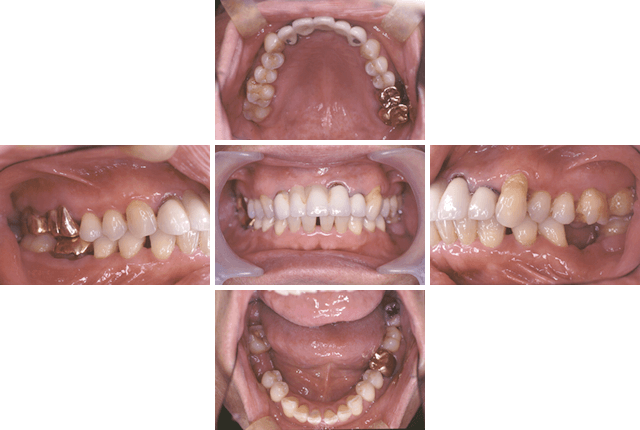

失われた歯の数、インプラントを埋め込む骨の硬さ、大きさ、位置により、治療法にはさまざまな選択肢があります。歯にかかる力の方向や強さはもちろん、患者さんに無理のない衛生管理などを含め総合的に検討した上で、治療計画が立てられます。

当院では、幅広いケースや症例に対応したインプラント治療法を導入しております。

「骨の量が足りないので難しいと言われた」「あごの骨を削りたくない」「手術が怖い」などの理由で治療を諦めていた方も、ぜひ一度当院にご相談ください。